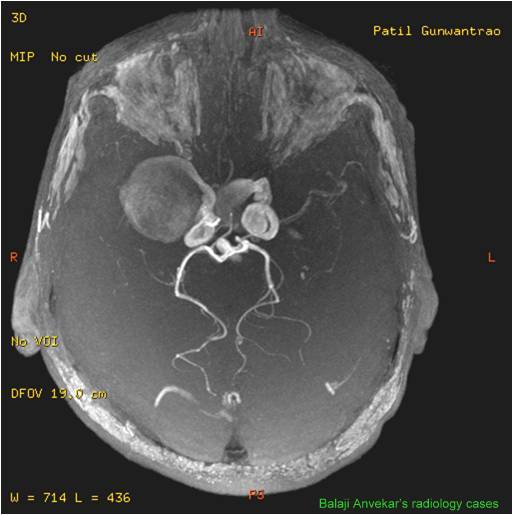

From www.neuroradiologycases.com

Dr Balaji Anvekar FRCR Bilateral ICA aneurysms MR Angio Aneurysm Coils And Mri in the clinical magnetic resonance imaging (mri) setting, it is often necessary to manage patients with embolization coils. Titanium alloy) have been tested and shown to be safe for patients undergoing mr. mr imaging, mr angiography, and functional mri are frequently used to evaluate the brain or cerebral vasculature of patients with. coil embolization is currently the. Aneurysm Coils And Mri.